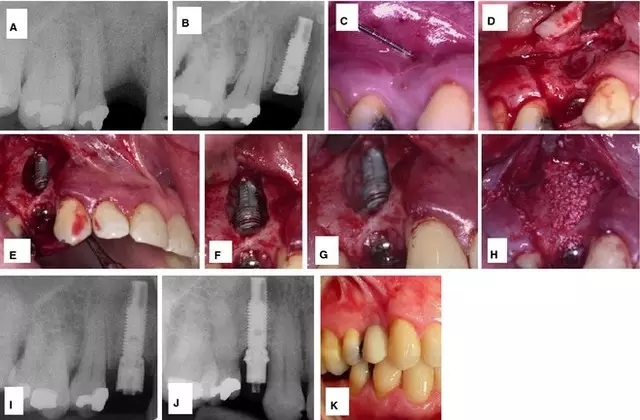

此外,也有學者應用凍干骨和膠原膜也成功修復了骨缺損。但是 Balshi 等學者認為相比引導骨再生,手術(shù)切除感染種植體的根尖區(qū)是更好的治療方法。他們的治療程序如圖 2:】

圖 2 :(A)種植體植入后即刻負載三月后的根尖周 x 線片;(B–E)移除 21,切除 23 根尖 ;(F)術(shù)后調(diào)整和修復; (G) 術(shù)后口內(nèi) x 線片;(H–J)種植體根尖切除后 2 (H)、4 (I)、 6 (J)年的曲面斷層